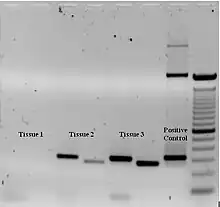

- CMV DNA capture ( polymerase chain reaction (PCR) test)

- DNA PCR ( ocular fluids)